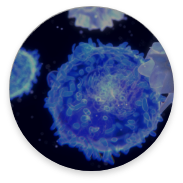

NK cell

Dendritic cell

T cell

iNKT cell